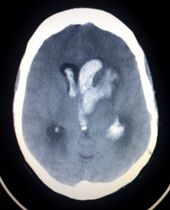

السكتة النزيفية Hemorrhagic stroke

CT scan showing an intracerebral hemorrhage.

سكتة نتيجة نزيف في المخ:

ويعني تجمع الدم في أي مكان ضمن الجمجمة ويظهر في صورة صداع ويكون نتيجة كدمة بالرأس

أو نزيف داخل المخ Intracerebral haemorrhage